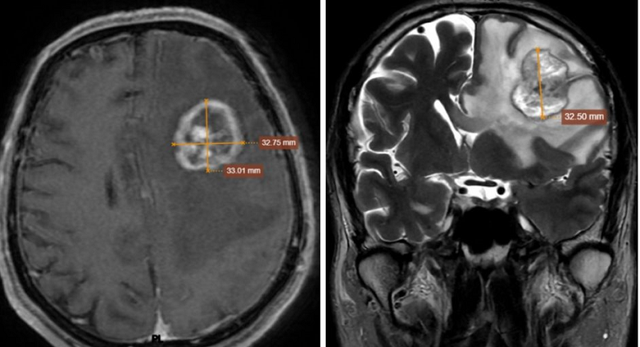

Chụp MRI sọ não có khối choán chỗ vùng thái dương - đỉnh trái, kích thước 32x33x32mm. Ảnh: BVCC

Kết quả chụp MRI phát hiện một khối u lớn vùng thái dương – đỉnh trái, kích thước khoảng 32 mm, kèm nhiều tổn thương rải rác ở cả hai bán cầu não và màng não. Tình trạng phù não lan rộng, gây chèn ép và đẩy lệch đường giữa gần 8 mm – dấu hiệu nguy hiểm có thể đe dọa tính mạng.